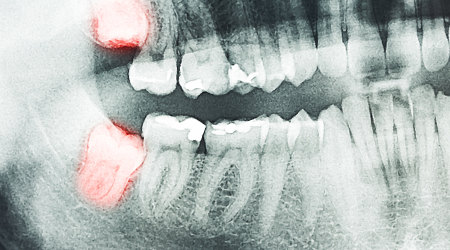

Non Surgical Tooth Extraction 1000 15

Procedure INR US

Surgical Tooth Extraction 4000-10000 60-155

SINUS LIFT PROCEDURE

Technique INR US

Indirect 22000 350

Direct SINUS LIFT Procedure 50000 775